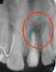

X-ray showing

picture line